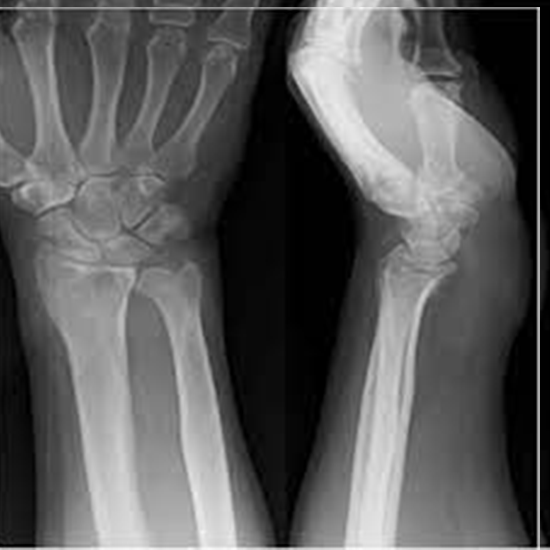

X-ray Both Wrist AP View

X-Ray View of the Right Wrist AP view utilizes a small amount of radiation while assisting in the visualization of the wrist. Two of the bones in the forearm (the radius and the ulna) plus eight smaller bones make up the wrist (carpal bones). You should do so if you have symptoms such as pain, tenderness, or swelling in your feet.

It is beneficial in diagnosing infections, cysts, tumors, and other disorders that may be present in the wrist bones. It is also done to evaluate the alignment of bones after surgery or as part of a study on bone aging before surgery.